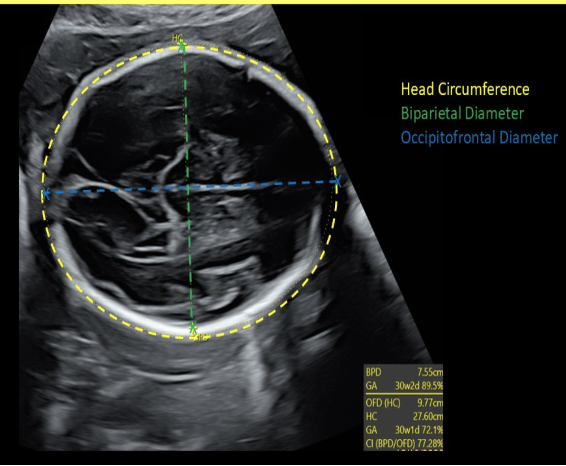

how to properly perform the occitpital-frontal (OFD) measurement of a fetus

b) axial view of fetal head w/calipers placed from outer frontal edge to outer occipital edge of the cranium

BPD measurements are taken from ____ edge of the skull to ___ edge of the skull

b) outer, inner

the correct cranial level for BPD + HC assessment is

a) Transverse axial view of the fetal skull at the level of the cavum septum pellucidum, third ventricle, and thalamus

the OFD of the skull is measured from ___ edge of the skull to the ___ edge of the skull

d) outer, outer